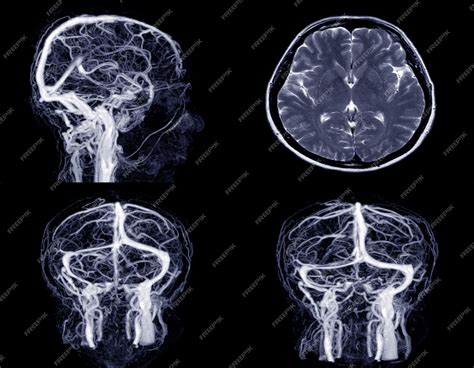

Magnetic Resonance Venography (MRV) is a sophisticated medical imaging technique that uses magnetic fields and radio waves to generate detailed images of the cerebral veins. Unlike a standard MRI, which primarily looks at the brain tissue itself, an MRV is specifically designed to assess blood flow and identify potential abnormalities within the venous system.

The core technology behind an MRV is the same as a standard MRI machine—a large tube surrounded by a powerful circular magnet. For an MRV, the process is often enhanced with the use of a gadolinium-based contrast agent. This contrast dye is injected into a vein in your arm, which helps the blood vessels "light up" on the resulting images, providing a clear contrast between the vessels and the surrounding brain tissue.

The imaging machine detects the signals emitted by the blood flow within these enhanced vessels, creating a high-resolution map of the venous drainage system. The entire process is non-invasive, meaning no surgical intervention is required.